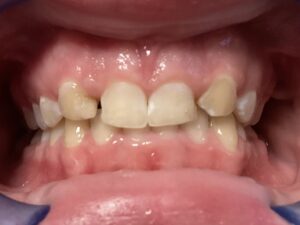

This patient arrived at my practice last week with 2 congenitally missing laterals incisors. Her orthodontist moved the canines into the position of the lateral incisors to fill the gaps but canines don’t look like incisors. They are pointy and “fat” so I told them upfront that although perfect aesthetics will not be achieved we can greatly improve the look and also remove the decay. The procedure required a single 2hr appointment and a very pleasing result was achieved with a very happy teenager leaving the practice that day. Further improvements can be done at a next visit by removing the white spots on the first premolars.